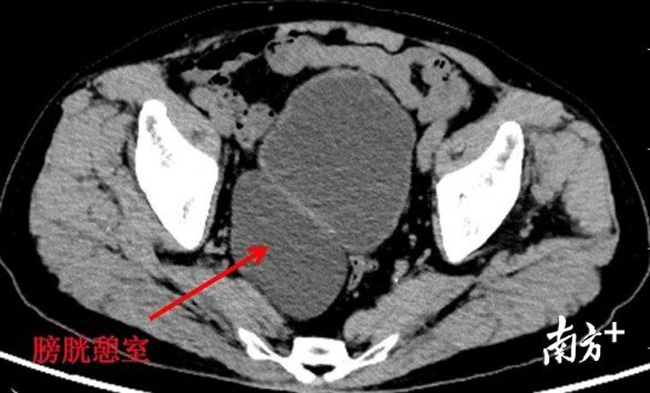

Qua siêu âm Doppler bác sĩ Đới nhận thấy sau khi đi tiểu xong bàng quang bệnh nhân vẫn còn chưa tới 500ml nước tiểu, chẩn đoán ban đầu là bị tăng sản tuyến tiền liệt lành tính. Thế nhưng sau đó, bác sĩ phát hiện bệnh nhân thực sự có thêm một bàng quang khác.

Bác sĩ Đới cho biết bệnh nhân có một phần nhô ra giống như vòng bít có đường kính gần 10 cm sau bàng quang. Nguyên nhân của tình trạng này được cho là do tiểu rắc làm tăng áp lực lên bàng quang. Thêm vào đó, tăng sản tuyến tiền liệt cũng là nguyên nhân chính gây ra tình trạng trên. Nếu không được chẩn đoán và điều trị kịp thời, bàng quang thứ 2 này sẽ gây ra nhiều biến chứng như sỏi, khối u và làm cho chức năng chính của bàng quang bị suy yếu.

Bàng quang thứ 2 được xác định là một sự thay đổi bệnh lý của bàng quang. Nó là một túi thừa phình ra khỏi niêm mạc bàng quang, thông qua lớp cơ của thành bàng quang chính. Cái túi thừa này giống như da nhưng không co giãn. Nó không thể co bóp, dẫn tới nước tiểu bên trong không thoát ra được, có khả năng đi kèm với trào ngược bàng quang niệu quản.